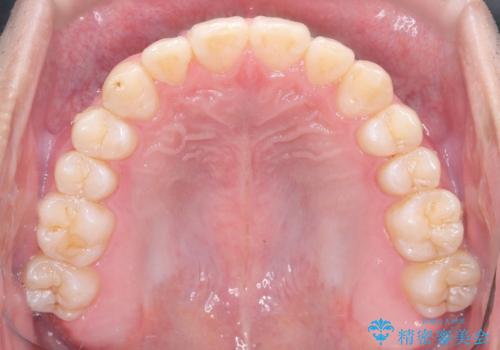

- 八重歯が気になるとのことでご来院されました。お口の中を確認すると、上の前歯がスペース不足で押し出され、少し前に出ている状態でした。抜歯せずに整えるため、奥歯を少しずつ後ろに動かしながら(遠心移動)、歯と歯の間をわずかに削るIPRを行ってスペースを作ることにしました。また、上下の噛み合わせを整えるために2級ゴム(エラスティック)を使用する方針を立てました。

マウスピースを段階的に交換しながら、奥歯を少しずつ後ろへ動かし、八重歯がきれいに並ぶよう調整しました。前歯の突出感を抑えるためにIPRを行い、スムーズに配列。さらに、2級ゴムを活用して噛み合わせも改善しました。治療後は、自然な歯並びになり、笑顔に自信が持てるようになったと喜んでいただきました。